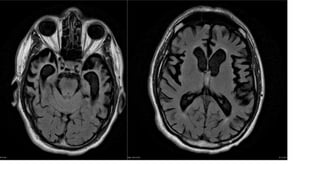

RADIOGRAPHIC FEATURES

MRI

Atrophy in various parts of the brain without a clearly identified unique

pattern.

Most helpful in distinguishing DLB from other entities resulting in dementia

is the absence of features of other diseases.

generalised decrease in cerebral volume most marked in

frontal lobes ; parietotemporal regions ;

enlargement of the lateral ventricles

relatively focal atrophy

midbrain

hypothalamus